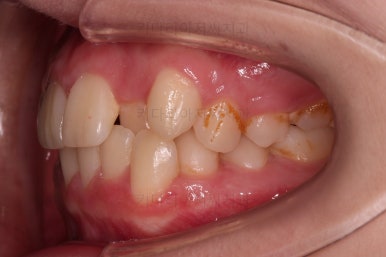

덧니도 개선되었고 가지런한 느낌도 좋네요.

교합도 좋고, 평행하지 않던 느낌도 많이 좋아졌습니다.